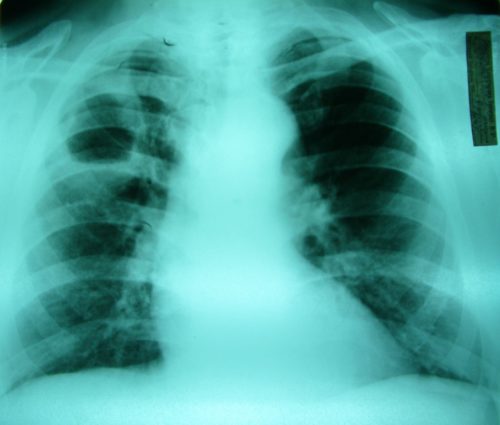

- Бронхит или пневмония – это нарушение дыхательной функции. Распознается по высокой температуре тела, усиленному кашлю и одышке.

Крупозная пневмония

Заболевание легких, которое сопровождается острым воспалением легочной ткани, называется острой крупозной пневмонией. Чаще всего болезнь поражает две стороны ткани одновременно, что дает выраженные симптомы отравления. Заболевание характеризуется вторичным изменением внутренних органов, что может привести к опасным последствиям.

При отсутствии грамотного и комплексного лечения заболевание становится причиной летального исхода, так как поражает всю дыхательную систему и работу сердечно-сосудистого отдела. Этот процесс всегда приводит к гипоксии в головном мозге.

Двустороннее воспаление вызывает сильный кашель, который затрагивает верхние гортанные и блуждающие нервы. Этот процесс вызывает кровянистые выделения, из-за которых больной испытывает сильный дискомфорт.

Крупозная пневмония сопровождается острыми симптомами:

- непродуктивный кашель;

- ржавая мокрота;

- кровянистые выделения;

- металлический привкус во рту;

- одышка;

- учащение дыхания;

- боль в груди.

Туберкулез

Туберкулез является частой причиной кровянистых выделений и неприятного привкуса во рту. Воспаление передается воздушно-капельным путем, поэтому заболеть может любой. В группу риска входят люди со слабым иммунитетом, плохим питанием и неблагоприятными условиями жизни.

Как правило, туберкулез сопровождается острым кашлем, который может беспокоить больного более двух недель. В это время отмечаются боли за грудиной, выделения с кровянистыми прожилками, истечение большого количества мокроты. Кроме того, отмечается резкое похудание, лихорадка, слабость, вялость, потливость.

Отсутствие лечения туберкулеза может привести к опасным последствиям, вплоть до летального исхода больного. При правильной диагностике и своевременном лечении избавиться от воспаления можно за месяц, но не исключен рецидив заболевания через несколько лет. По этой причине больные туберкулезом должны следить за своим питанием, образом жизни и иммунной системой.